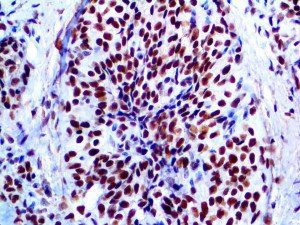

It is the ICU physician who is most likely to witness one of the deadliest manifestations of the abnormal immunological response, the cytokine storm syndrome (CSS). This response is also referred to by some as the cytokine release syndrome (CRS). CSS is characterized by continuous activation and expansion of macrophage and lymphocyte populations, which secrete large amounts of cytokines, causing the cytokine storm. This massive cytokine release is akin to hemophagocytic lymphohistiocytosis (HLH) disease, a syndrome characterized by initial unchecked and persistent activation of cytotoxic T lymphocytes and NK cells.

Clinical and laboratory manifestations of HLH include fever, enlarged liver and/or spleen, neurologic dysfunction, coagulopathy, liver dysfunction, cytopenias (i.e., low levels of erythrocytes, leukocytes, and/or platelets), hypertriglyceridemia, hyperferritinemia, hemophagocytosis, and eventually diminished NK cell activity as the immune system becomes progressively paralyzed. HLH can be familial (primary HLH) or secondary to another disease process (sHLH), such as rheumatic disease, in which it is referred to as macrophage activation syndrome (MAS, characterized by elevated ferritin).